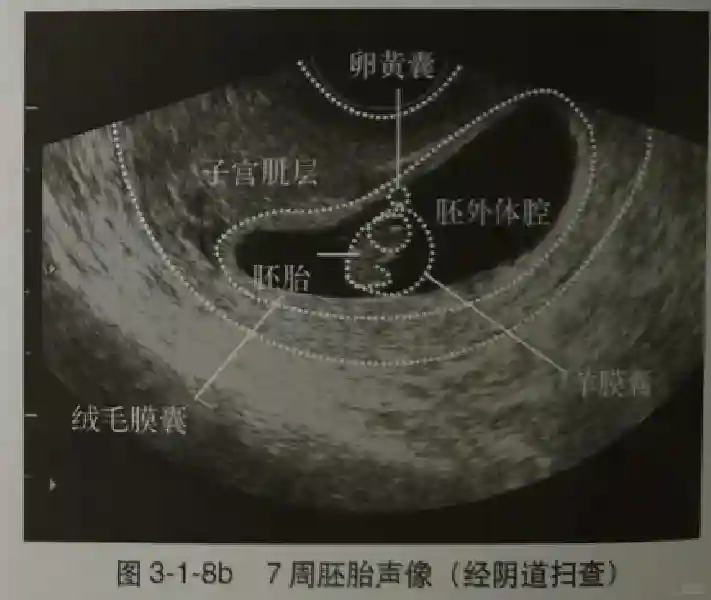

2??卵黃囊:是妊娠囊內(nèi)第一個(gè)解剖結(jié)構(gòu),直徑<7mm。表現(xiàn)為小環(huán)狀,中央為無(wú)回聲,囊壁薄,內(nèi)透聲好。卵黃囊位于胚胎旁胚外體腔內(nèi)。卵黃囊通常在孕5-6周時(shí)出現(xiàn),5-10周穩(wěn)步增長(zhǎng),一般不超過(guò)7mm,至12周消失。妊娠囊的大小與卵黃囊之間有一定關(guān)系,妊娠囊平均直徑> 8 mm 時(shí),經(jīng)陰道超聲均應(yīng)顯示卵黃囊,妊娠囊平均直徑> 18 mm 時(shí),經(jīng)腹超聲均應(yīng)顯示卵黃囊。

3??胚胎:胚胎通常在6-7周時(shí)可以為超聲顯示,起初為胎芽,表現(xiàn)為卵黃囊一側(cè)局部組織增厚,達(dá)到1 -2 mm 時(shí)才有可能為超聲測(cè)量出來(lái)。達(dá)4-5mm時(shí)可見(jiàn)胎心搏動(dòng),相應(yīng)孕周為6-6.5周,妊娠囊大小為13-18mm。胚芽長(zhǎng)度≥7㎜時(shí)仍未見(jiàn)心管搏動(dòng),提示胚胎停止發(fā)育。胚胎的出現(xiàn)和妊娠囊直徑的關(guān)系:妊娠囊直徑> 16 mm 時(shí),經(jīng)陰道超聲應(yīng)顯示胚胎。妊娠囊直徑> 25 mm 時(shí),經(jīng)腹超聲均應(yīng)顯示胚胎。

5??羊膜:早孕期羊膜囊菲薄,超聲常不能顯示。孕7周以后加大增益或者用高頻超聲可以顯示羊膜。羊膜囊位于絨毛膜內(nèi),胚胎位于羊膜囊內(nèi)。隨著胚胎增長(zhǎng),羊水增多,羊膜囊增大,孕12-16周時(shí),羊膜與絨毛膜全部融合,胚外體腔消失。宮腔線(xiàn)一側(cè)內(nèi)膜內(nèi)一圓形增強(qiáng)回聲區(qū),中央有小囊狀液性暗區(qū),宮腔線(xiàn)局部突起變形,稱(chēng)蛻膜內(nèi)征,用于判斷早早孕。